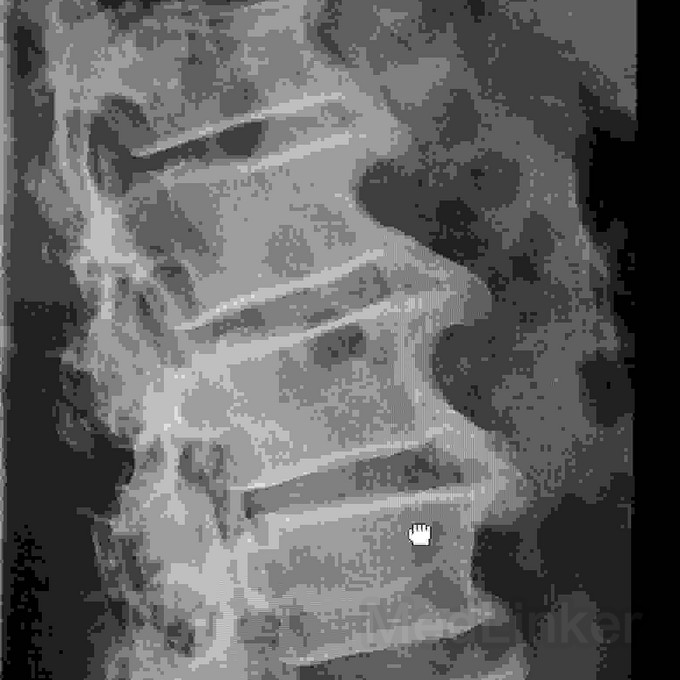

腰椎正侧位片描述?

患者男,59岁,腰痛1年来就诊,行腰椎正侧位片(见图),因我基层医院刚刚开展Dr摄影技术,且缺乏有资质的影像诊断医师,在描述和诊断此片时遇到难题,望贵人指教,谢过!